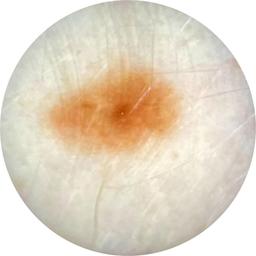

ISIC_4698082

Clinical

Field Value

acquisition_day 92

age_approx 35

anatom_site_1 Trunk

anatom_site_2 Posterior trunk

anatom_site_general posterior torso

concomitant_biopsy False

diagnosis_1 Benign

diagnosis_confirm_type single image expert consensus

family_hx_mm False

fitzpatrick_skin_type I

image_manipulation instrument only

image_type dermoscopic

lesion_id IL_0295269

patient_id IP_6143425

personal_hx_mm True

sex female